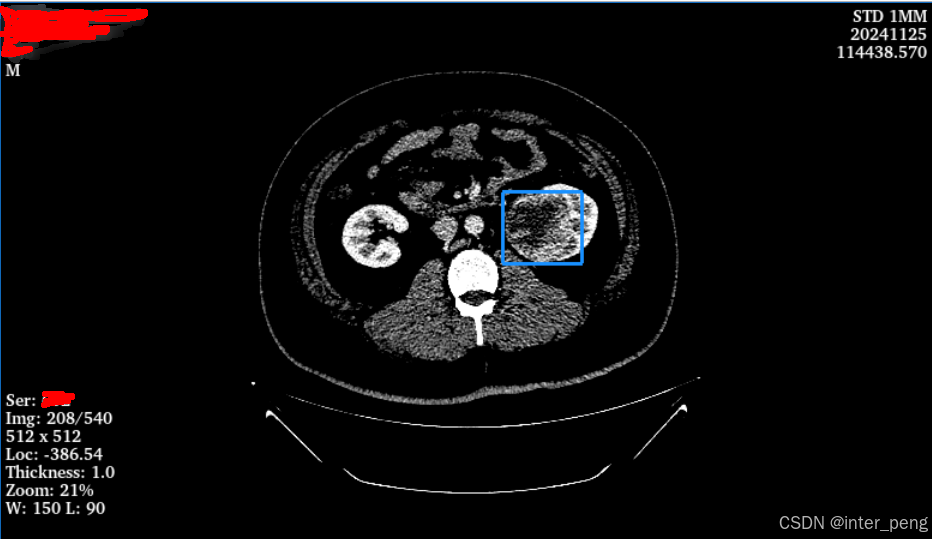

但是这里的黑屏,并不是图像不存在。其实图像是存在的,只不过按照我们预设的窗宽窗位,它显示出来是黑屏。但是,通过切换不同的窗宽窗位的预设,比如从胸腹窗,切换到肺窗以后,是可以看到图像的轮廓的,但是图像整体上仍然是偏暗的。

其次,当我将这个序列生成的体数据,放到slicer里面时,slicer是可以显示出来这个序列的,而且看起来还比较“正常”。

至少,在肉眼看起来,看不太明显它有什么问题。

其实,之所以这个有问题的序列,在我们的软件产品中黑屏,而在slicer, 或其他的一些dicom viewer里面能够正常展示。是因为,这些软件,它们会根据这个序列的灰度范围,而自动调节显示时使用的窗宽窗位。而我们的软件,由于是给特定部位使用的,所以里面有一个默认的窗宽窗位,就像第一幅图中展示的, ww = 150, wl = 90.